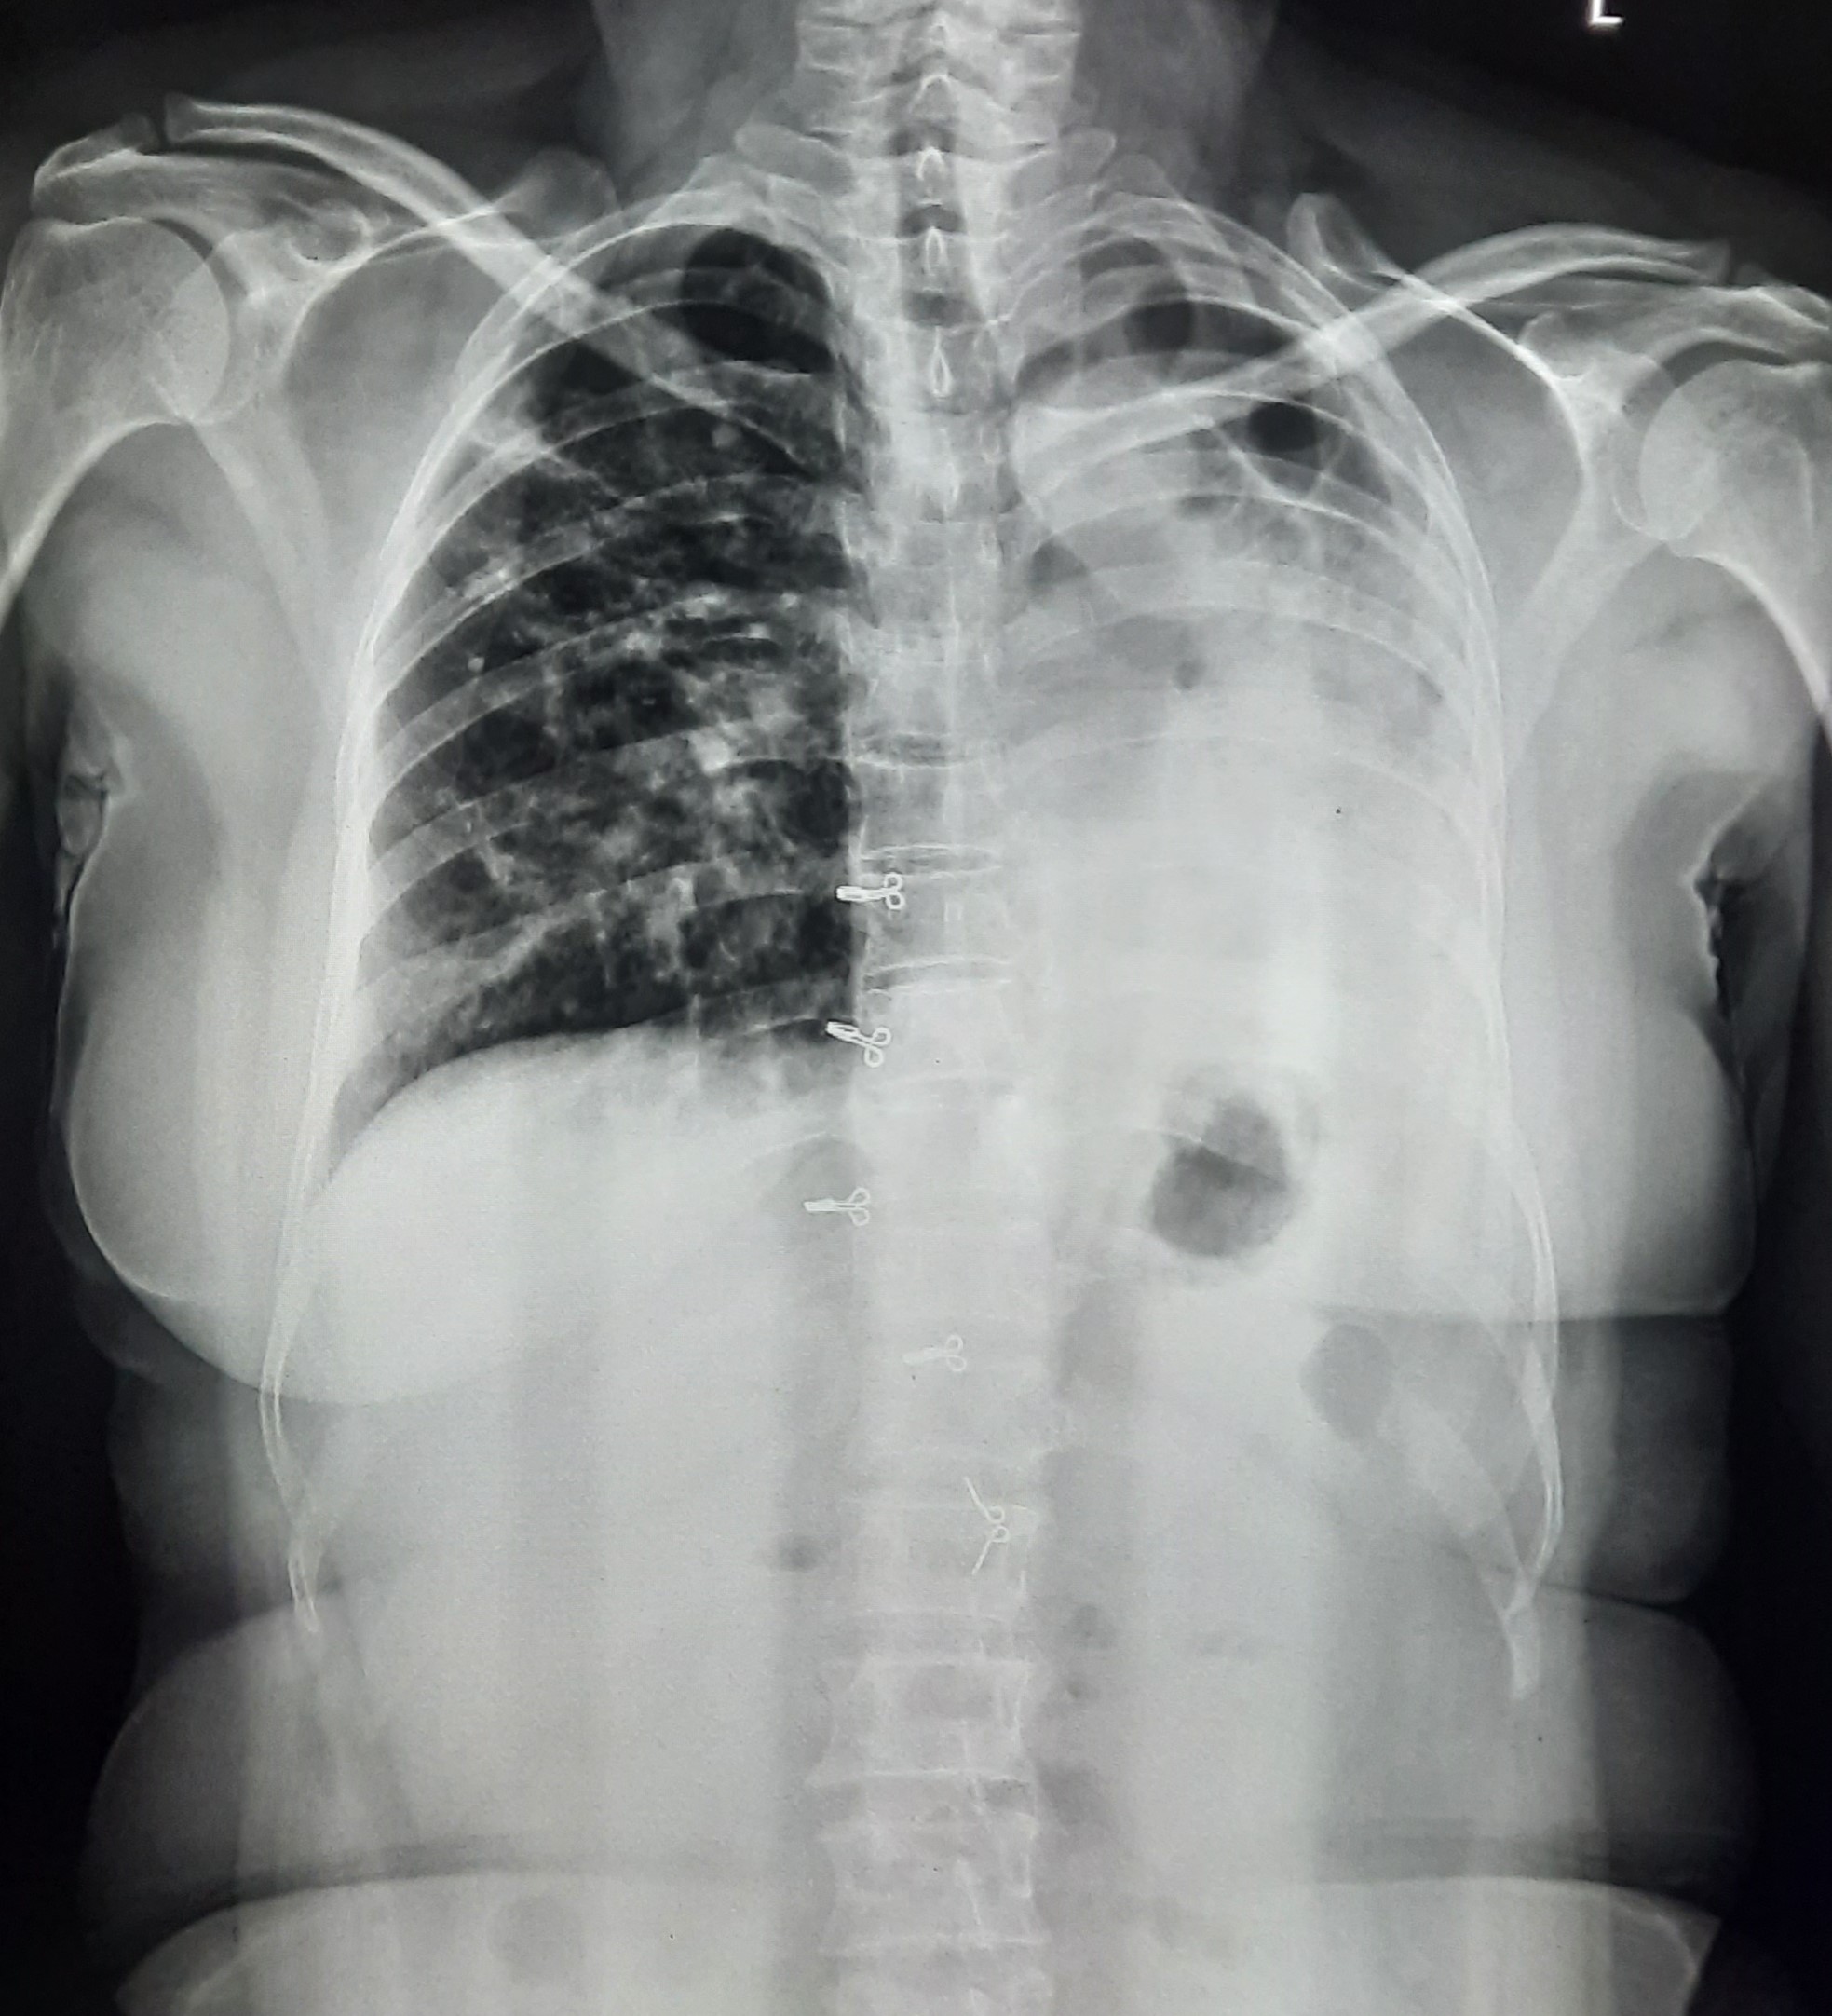

| 127 | IGGMC, Nagpur, Nagpur | P2 | 29-4345 | Hiraman Tembhurne | Consent taken on Paper | 62 Yrs. |

Provisional Diag : Dyspnea

Final Diag : Post TB With Interstitial Lung Disease |

Post TB Sequelae | Bilateral Cystic Opacity Upper, Mid & Lower Zone/ Bilateral Reticular Opacites/ Bilateral Fibrotic Bands Present/ Decrease Lung Volume/ Few Old Calcific Nodules | Abnormality visible on x-ray |